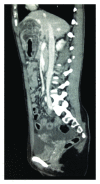

Hydatid cyst rupture into the abdomen is a serious complication of cystic hydatid disease of the liver (Cystic Echinococcosis) with an incidence of up to 16% in some series and can result in anaphylaxis or anaphylactoid reactions in up to 12.5% of cases. At presentation, 36-40% of hydatid cysts have ruptured or become secondarily infected. Rupture can be microscopic or macroscopic and can be fatal without surgery. Hydatid disease of the liver is primarily caused by the tapeworm Echinococcus granulosus and occurs worldwide, with incidence of up to 200 per 100,000 in endemic areas. Our case describes a 24-year-old Bulgarian woman presenting with epigastric pain and evidence of anaphylaxis. Abdominal CT demonstrated a ruptured hydatid cyst in the left lobe of the liver. A partial left lobe hepatectomy, cholecystectomy, and peritoneal washout was performed with good effect. She was treated for anaphylaxis and received antihelminthic treatment with Albendazole and Praziquantel. She made a good recovery following surgery and medical treatment and was well on follow-up. Intraperitoneal rupture with anaphylaxis is a rare occurrence, and there do not seem to be any reported cases from UK centres prior to this.